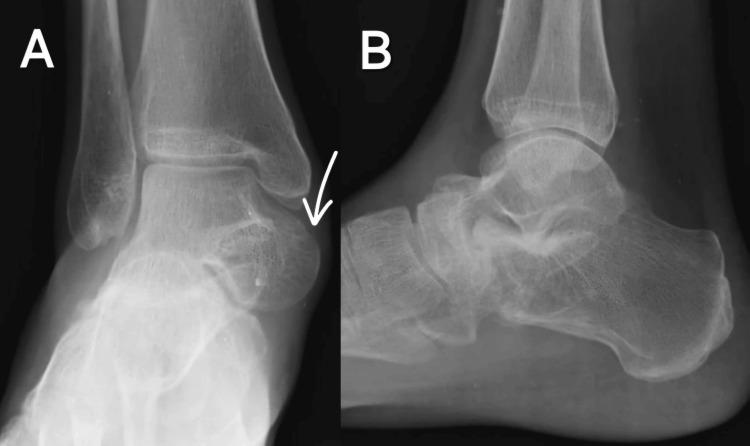

The complete loss of articular relationships between the talus and navicular bone is known as talonavicular joint (TNJ) dislocation. Medial dislocation of the TNJ is more common than lateral dislocation. Lateral dislocation is usually associated with a fracture of the calcaneocuboid joint. Surgeons encounter difficulties when treating these dislocations. It occurs following high-energy trauma and is managed with immediate closed reduction of the joint and immobilization, but some complicated cases require open reduction and fixation to achieve alignment, strength, and function. This case report describes a six-month-old neglected case of TNJ dislocation managed with corrective osteotomy and subtalar fixation. Fusion of the talonavicular and talocalcaneal joints was performed. This procedure had a satisfactory outcome, as the patient was completely relieved of pain.

距骨与舟状骨之间关节关系完全丧失被称为距舟关节(TNJ)脱位。TNJ内侧脱位比外侧脱位更常见。外侧脱位通常与跟骰关节骨折相关。外科医生在治疗这些脱位时会遇到困难。它发生于高能创伤后,通过立即进行关节闭合复位和固定来处理,但一些复杂病例需要切开复位和固定以实现对线、强度和功能。本病例报告描述了一例六个月大被忽视的TNJ脱位病例,采用矫正截骨术和距下固定进行治疗。同时进行了距舟关节和距跟关节融合术。该手术取得了满意的效果,患者疼痛完全缓解。